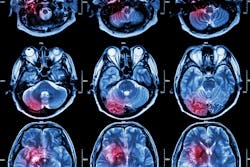

Stroke patients who survive a blood clot in the brain’s blood vessels are prone to developing new blockages during their recovery periods, even if they receive vessel-clearing interventions.